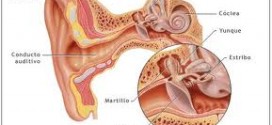

Leer MásMELANOMA DEL OIDO

El melanoma del oído. El oído es el órgano responsable no sólo de la audición sino también del equilibrio. Se divide en tres zonas: externa, media e interna. La mayor parte del oído interno está rodeada por el hueso temporal. Durante los primeros años de vida de una persona, las células normales se dividen más rápidamente para permitir el crecimiento. …